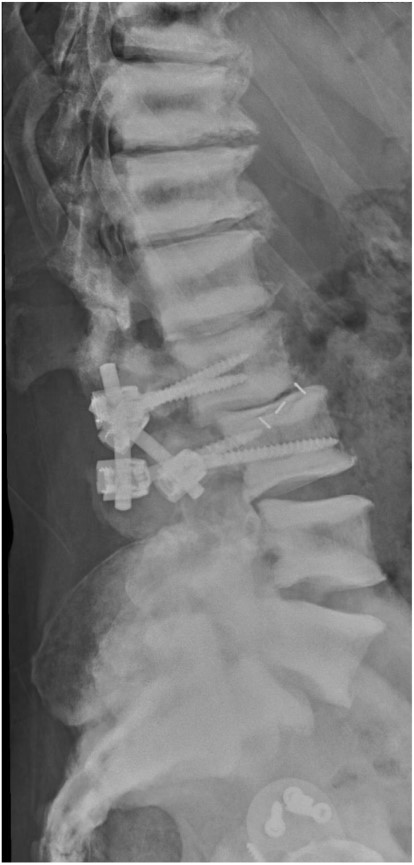

Six months later, he complained about lumbar pain which irradiated into the right thigh and knee. A CT scan of the lumbar spine showed multiple lumbar spine stress fractures, and CT myelography showed complete obstruction at L2–3 level (Figs 4 and 5). Conservative therapy was ineffective. Therefore, the patient was transferred to a spinal center. There he underwent L2–L3 decompression with short-term effect because decompression resulted in instability. 360° spondylodesis was done; however, it resulted in non-union, and the material was removed (Fig. 6).

Sagittal view of CT lumbar spine myelography. Note also the density of sclerotic bone.

Lateral radiograph of the lumbar spine after failed 360° spondylodesis.